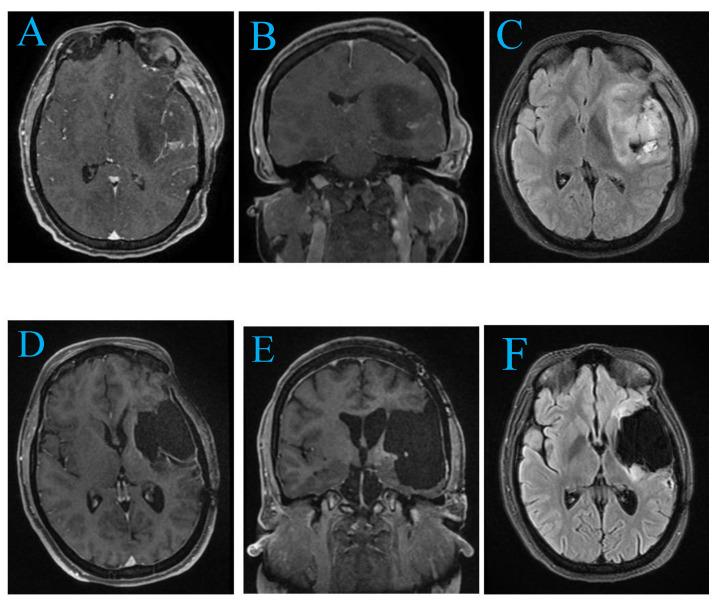

From 156 studies, 11 met inclusion criteria, highlighting advanced diagnostics, surgical strategies, and adjunct therapies for temporo-insular gliomas (TIGs). Gross total resection (GTR) was achieved in 39% of cases. Awake craniotomy enhanced functional outcomes, while temozolomide and radiotherapy improved survival. Challenges included ischemic complications and treatment resistance. Two patient cases underscored the complexity of TIG management and the importance of individualized approaches, achieving satisfactory resection with minimal deficits.

从156项研究中,11项符合纳入标准,突出了颞岛胶质瘤(TIGs)的先进诊断、手术策略和辅助治疗。39%的病例实现了大体全切(GTR)。清醒开颅手术改善了功能结局,而替莫唑胺和放疗提高了生存率。挑战包括缺血性并发症和治疗耐药性。两个患者病例强调了TIG治疗的复杂性以及个体化方法的重要性,在最小程度的功能缺损下实现了满意的切除。